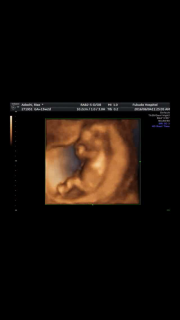

頭抱えるように寝てました!しっかり心臓も動いてて、7センチ! 頑張って大きくなってくれてます。 今度は、1ヶ月後に会いましょう♪

検診行ってきました。 赤ちゃんめちゃくちゃ元気に動いてました(笑) 7cmまで成長してました(^ω^)